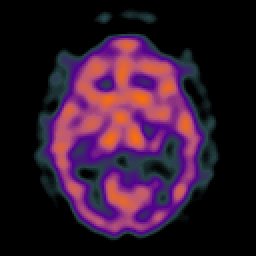

Glioma overlay -- Slice #13

[Home][Help][Clinical] Slice 13